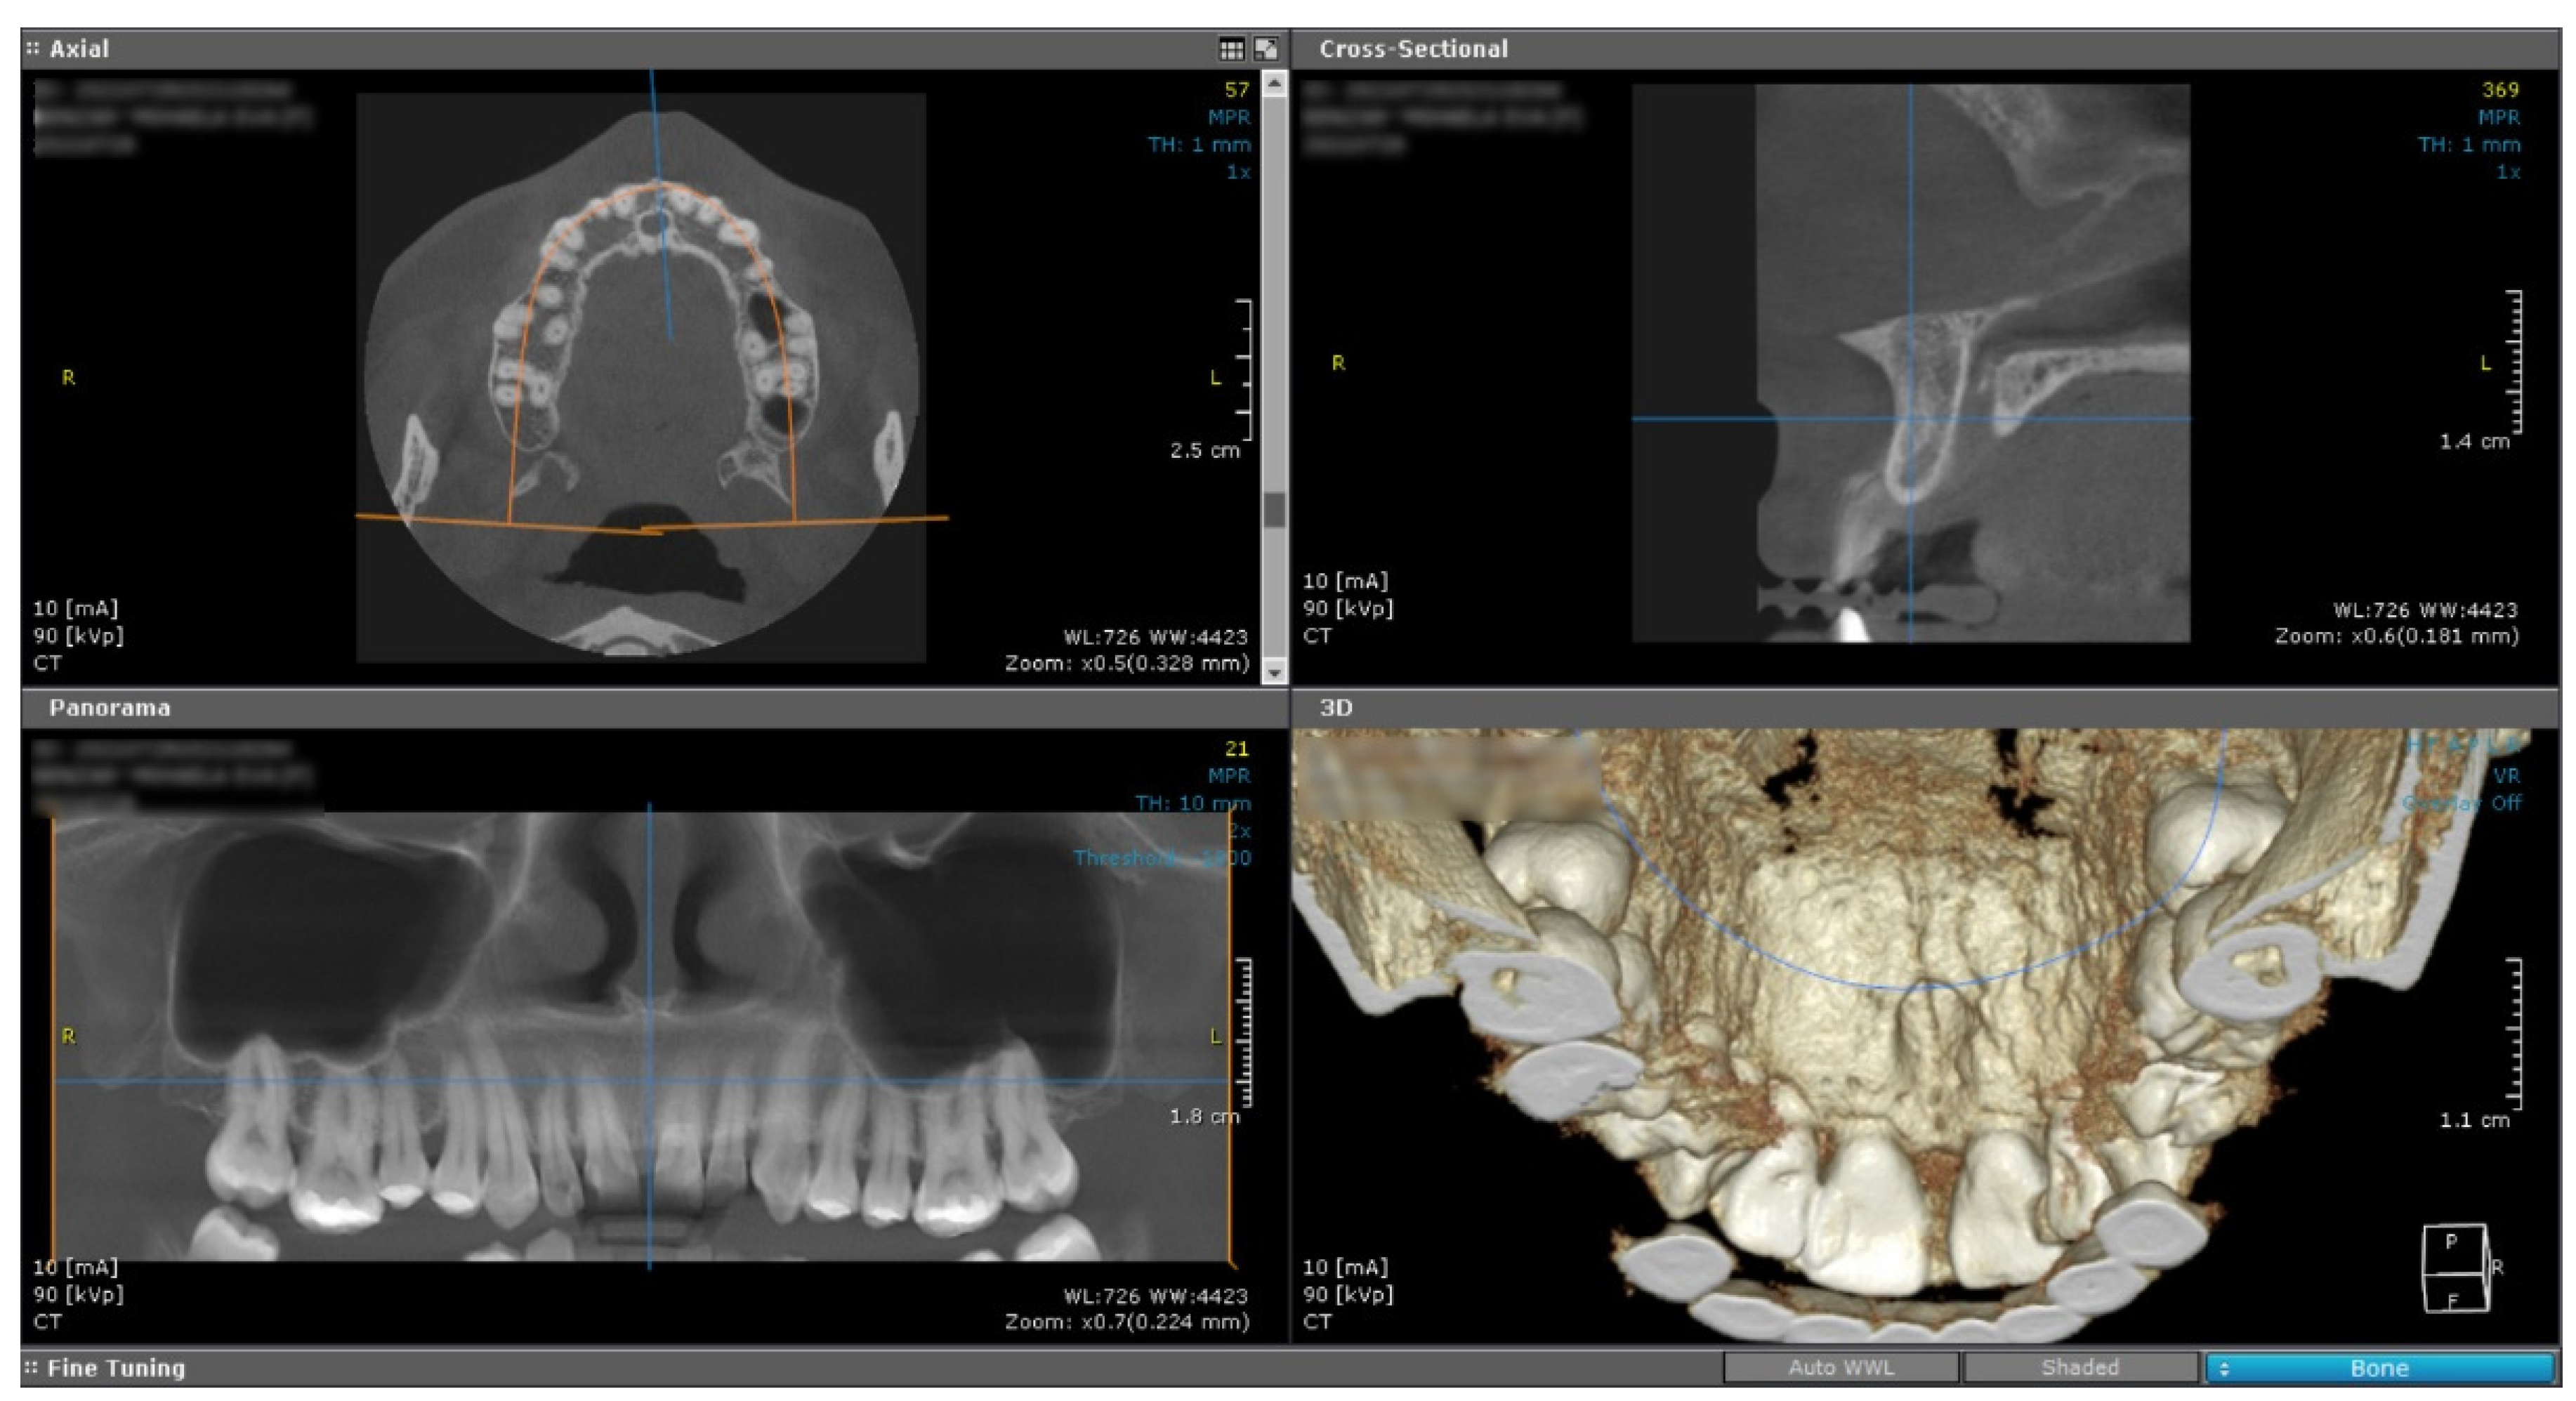

An intense and diffuse positive immunohistochemical reaction in all the tumor cells was found for desmin with a cytoplasmic pattern (Figure 4). In addition, smooth muscle actin was intensely positive in all the tumor cells with a cytoplasmic and nuclear pattern of distribution (Figure 5). On the other hand, vimentin was negative, with positive internal control at the level of the connective tissue (Figure 6). The Ki67 cell proliferation index was 3%, with only a few tumor cells being positive (Figure 7).

Figure 4. Microscopic images of IHC reactions for desmin, ob. 40x: (a) tumor cells with diffuse and intense positive reaction for desmin; (b) intense and diffuse cytoplasmic positive reaction in all the tumor cells.